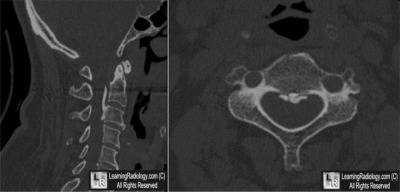

Additional Images - Sagittal and axial CT images of the cervical spine

Sagittal and axial CT images of the cervical spine

5. Ossification of the Posterior Longitudinal Ligament (OPLL)

Ossification of the Posterior Longitudinal Ligament (OPLL)

- Heterotopic ossification of the posterior longitudinal ligament

- Occurs primarily in cervical, most often C4-C5, next most commonly in thoracic spine and least frequently in lumbar spine

- Most commonly in 40s and 50s

- Twice as common in males as females

- Higher prevalence in Asian population, especially Japanese